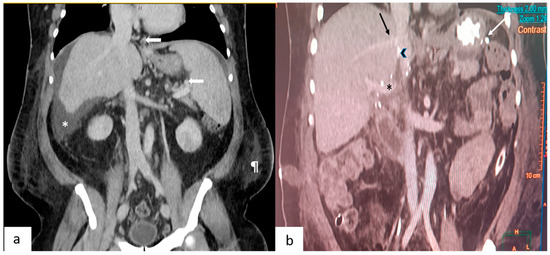

A recent systematic review by an expert panel [2] concluded that portal inflow modulation may help reduce morbidity/mortality in LDLT recipients with small-for-size grafts. This was a strong recommendation despite the evidence from the constituent studies (largely retrospective series) being of low quality. There are three ways to decrease the portal flow to the transplanted liver: splenic artery ligation, splenectomy, and hemi-portocaval shunts. The decision making process of portal flow modulation is described in a recent review [3]. In the authors’ institution, post reperfusion splenic artery ligation is the preferred strategy if portal pressure post reperfusion is more than 20 mm Hg or if flow is more than 350 mL/100 g of the liver tissue/min in a patient with GRWR < 0.8. If the estimated GRWR is <0.7, we would consider a pre-reperfusion splenectomy in select instances. Our group is not comfortable with hemiportocaval shunts. With the estimated GRWR being less than 0.6, and the MELD score being 23, a splenectomy was felt to be the best modality for inflow modulation in this setting to ensure reliable and maximum reduction in portal flow in a controlled manner. Although a hemiportocaval shunt is preferred by many groups, as it entails no additional dissection, we opted against this as it is difficult to precisely regulate how much blood goes into the graft. The pre-operative CT scan in the portal phase was studied carefully before this decision was taken. A massively enlarged spleen, dilated splenic vein and the relative absence of peri splenic collaterals were factors considered while making this decision (Figure 1a). The decision to perform a splenectomy prior to hepatectomy was a well thought-out pre-operative decision and was conveyed to the patient and the anesthesia team at the multidisciplinary meeting. We based this on the recent paper by Fujiki et al. [4], who reported excellent outcomes in their series of 130 LDLT, with SFSS developing in only one patient despite using small grafts. Twelve patients had very small grafts (GRWR < 0.6). In this subgroup, early allograft dysfunction occurred in two patients, one of them succumbing to sepsis due to bile leak. The authors have used the strategy for pre-reperfusion splenectomy for patients with GRWR < 0.7 [4]. We have adopted the same strategy in the index patient; this prevents exposure of the graft to sinusoidal injury post reperfusion and also prevents a hit to the graft due to hypotension if bleeding were to occur during the splenectomy. One-year graft outcomes seem to be better in small grafts with a pre-reperfusion splenectomy rather than post reperfusion splenectomy [4]. The Kyushu university group has been doing splenectomy for inflow modulation, especially while using left hemiliver grafts, for many years with good results, and no increase in morbidity. In a recent study [5], it has been shown with propensity score matching, that a splenectomy has a beneficial effect on graft survival when performed for post reperfusion portal pressures of more than 20 mm Hg. We elected to do the splenectomy first and obtained a satisfactory portal flow post reperfusion. The portal flow remained consistently within the normal range without hyperperfusion in the first post operative week; therefore, the hepatic artery buffer response was not pronounced. By this time, bilirubin and INR were normalizing and ascitic output was showing a downward trend, suggesting stable graft function.

Figure 1.

(a) This depicts a coronal section of a pre-operative contrast-enhanced CT scan. Arrows point to the gastroesophageal and splenic perihilar collaterals. Also seen are ascites (*) and the prominent subcutaneous fat (¶) in the flanks. (b) This depicts a coronal section of a post-operative CT scan performed on day 7. Seen are the junction of the right hepatic vein (black arrow), polytetrafluroethylene graft (arrowhead) with the inferior vena cava, portal vein (*) and vascular staplers (white arrow) used during splenectomy.